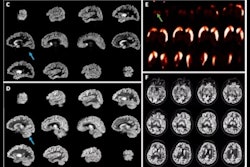

Top row: CT- and LSO-TX-based attenuation maps with their respective percentage relative change (%RC) map. Bottom row: PET images reconstructed using CT- and LSO-TX-based attenuation maps with their respective %RC map. Image and caption courtesy of the SNMMI.

The group observed close visual resemblance between CT- and LSO-TX-based attenuation maps and between PET images reconstructed with the maps. By using the LSO-TX-based attenuation correction alone (that is, no CT imaging), the total effective dose in these scans was reduced to approximately 0.15 mSV while "still preserving good quantitative accuracy and maintaining clinically feasible scan durations."

The investigators conducted a small study with four patients who received 7.9 MBq of radiotracer and underwent a 90-minute PET scan using a long axial field-of-view PET scanner; they also underwent low-dose CT (LDCT) imaging. They then generated CT-based and LSO-transmission-based attenuation maps to reconstruct PET images and compared these across a variety of scan lengths.